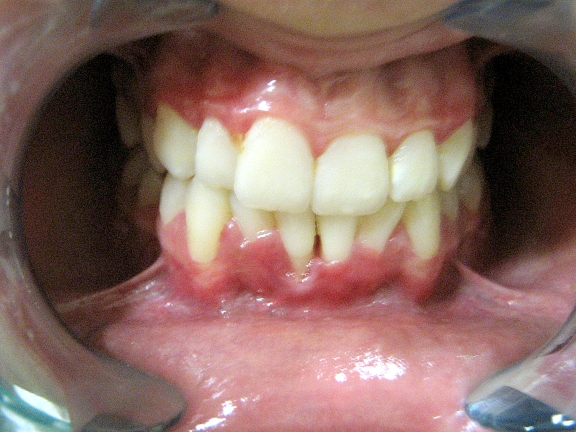

Clinical evaluation revealed gingival recession on the buccal surface extending 3 mm apical to the cemento-enamel junction (CEJ) and a narrow zone of attached gingival measuring approximately 1 mm (Figure 1). There was loss of papilla height on the mesial aspect of the incisor and moderate gingival overgrowth on the distal aspect. The gingiva in these regions had edematous, reddish and ulcerated appearance. Plaque deposits were minimal.

Figure 1.

Self-inflicted gingival recession with edematous and ulcerated margin due to 14-year-old girl’s scratching with fingernail.